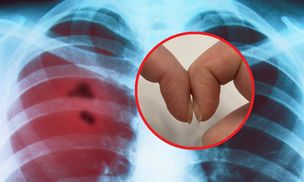

Występuje tuż po przebudzeniu. To często jedyny objaw rozwoju raka

Rak, który zabija Polaków. To jeden z jego objawów